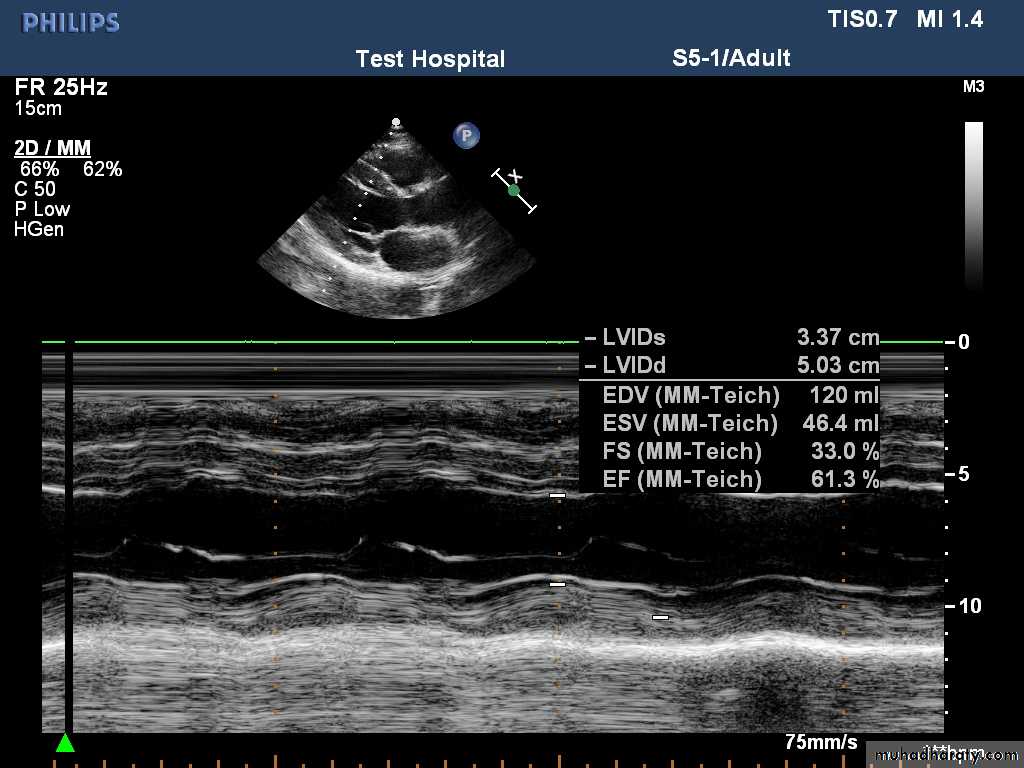

Echocardiography (echo)

Echocardiography, or cardiac ultrasound, is obtained by placing an ultrasound transducer on the chest wall to image the heart structures as a real-time, two dimensional ‘slic

Transthoracic echo.Transoesophageal echo.

Doppler echocardiography This depends on the Doppler principle that sound waves reflected from moving objects, such as intracardiac red blood cells, undergo a frequency shift. The speed and direction of the red cells, and thus of blood, can be detected in the heart chambers and great vessels